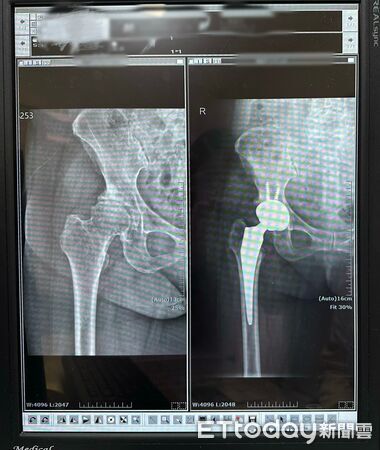

▲告別舉步維艱!嘉榮「正前開」人工髖關節置換術 讓患者術後當天即可下床走路 。(圖/嘉榮灣橋分院提供)

賴醫師指出,正前開人工髖關節置換術如同「撥開門簾進入室內,而非拆門而入」,因肌肉與肌腱得以完整保留,患者在術後初期即可感受到行動負擔減輕,對於提升復原速度與生活品質具有明顯助益,此外,正前開手術在精準度上也具優勢。醫師透過術中 X 光即時導引,確保人工關節置放於最佳位置,有效降低術後出現長短腳的風險。由於周邊肌肉包覆良好,患者術後對於姿勢與動作的限制相對較少,更有利於回歸日常生活。